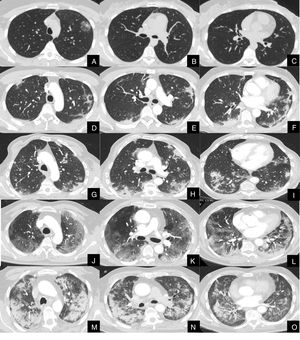

La severidad de la afectación parenquimatosa se clasificó visualmente según la extensión del parénquima afectado en 5 grados: grado 1, muy leve (1-5%), grado 2, leve (6-25%), grado 3, moderada, (26-50%), grado 4 severa (51-75%) y grado 5, muy severa (76-100%) (fig. 1).

Imágenes axiales de angioTC pulmonar en ventana de parénquima a nivel de lóbulos superiores, medios e inferiores, que muestran los diferentes grados de afectación parenquimatosa en pacientes con infección respiratoria por COVID-19.

A, B y C: grado muy leve. Opacidad redondeada en vidrio deslustrado con signo del halo invertido en lóbulo superior izquierdo.

D, E y F: grado leve. Consolidaciones parenquimatosas subpleurales de escasa cuantía y de predominio en segmentos posteriores de lóbulos inferiores.

G, H y I: grado moderado. Consolidaciones subpleurales más extensas que en el grado leve, con signo del halo invertido en lóbulo inferior derecho.

J, K y L: grado severo. Vidrio deslustrado extenso con afectación de todos los lóbulos pulmonares y consolidaciones en segmentos posteriores de ambos lóbulos inferiores.

M, N y O: grado muy severo. Extensas consolidaciones parenquimatosas de predominio periférico con afectación de casi la totalidad del parénquima pulmonar.